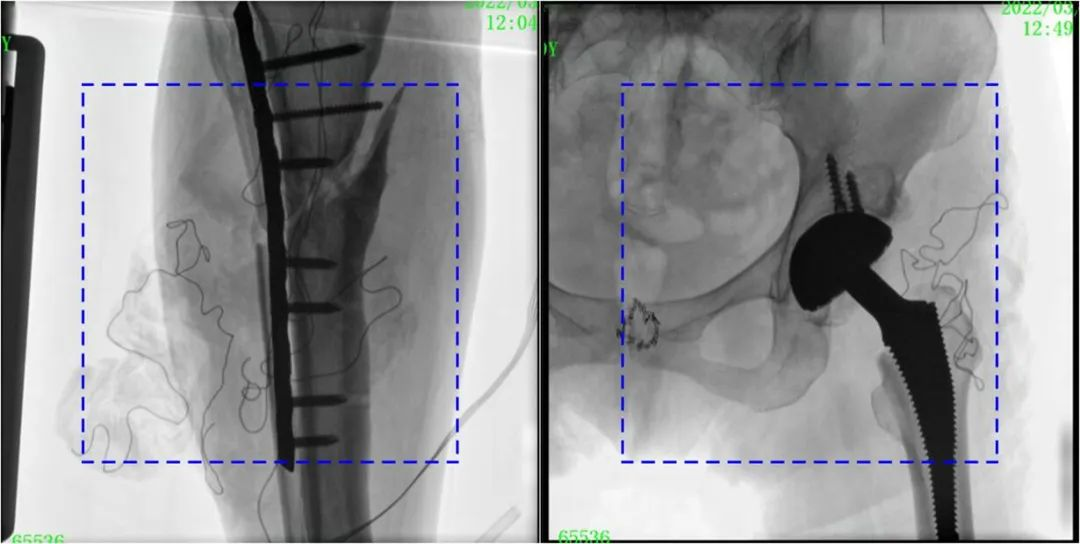

與傳統(tǒng)的21CM×21CM成像尺寸相比,普愛醫(yī)療大平板一體式C形臂具有30CM×30CM更大成像尺寸,能夠一次成像5.5節(jié)椎體,呈現(xiàn)更全面的影像信息,即便是手術(shù)經(jīng)驗不豐富的年輕醫(yī)生也能通過圖像迅速判斷椎體節(jié)段、定位手術(shù)部位,避免因為視野不足而造成的多次定位、反復曝光,提高效率的同時避免過量攝入輻射。

普愛醫(yī)療大平板一體式C形臂圖像與傳統(tǒng)圖像對比(藍色虛線內(nèi)為傳統(tǒng)21CM×21CM平板的成像區(qū)域)